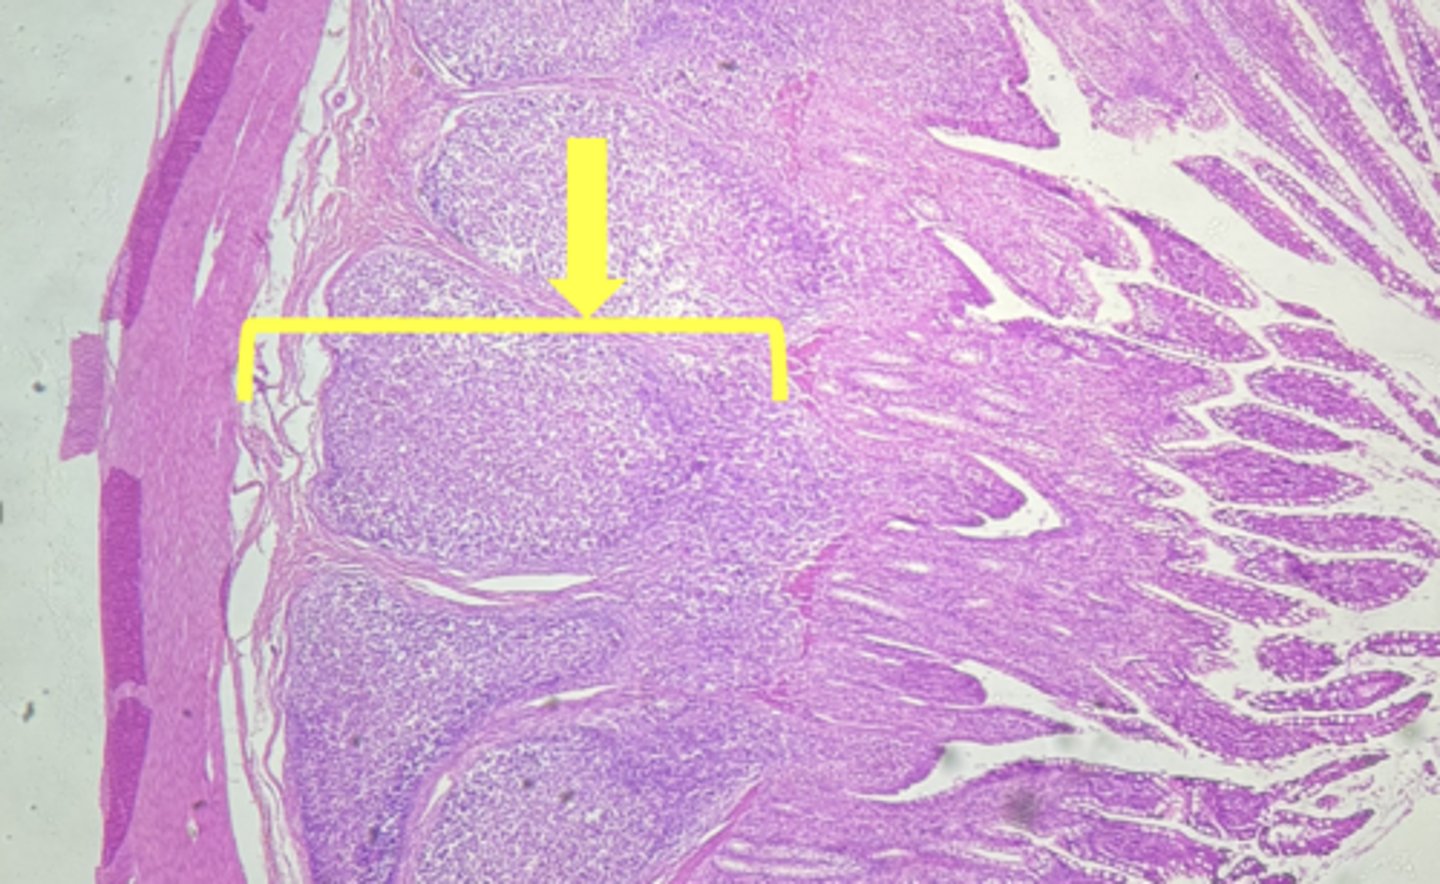

ileum-small intestine

type of tissue

Mucosa

(ilium)

submucosa

muscularis externa

payers patch (KEY CHARACTERISTIC)

circular layer

(ileum)

longitudinal layer

villi

simple columnar epithelium

type of cell

goblet cell- mucous (KEY CHARACTERISTIC)

(ileum-increased # seen here)

type of cell & what it secretes

intestinal crypts

lamina propria

muscularis mucosae